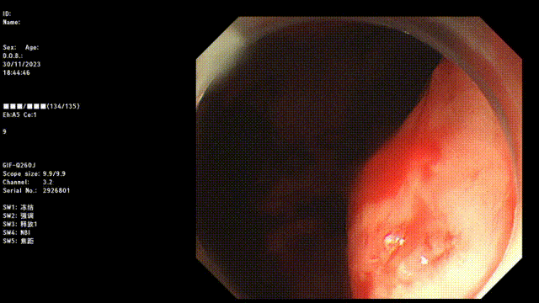

入冬以來,消化道出血進(jìn)入高發(fā)期。近期,臨沂金鑼醫(yī)院消化內(nèi)科收治了多例急性消化道出血患者,消化內(nèi)科主任姜開通(醫(yī)師)提醒:寒冷季節(jié),誘發(fā)部分有消化道疾病患者病情發(fā)作,特別是消化道出血,患者通常發(fā)病急、出血量大、可伴有失血性休克,甚至危及生命,請及時就醫(yī),送醫(yī)途中,嘔吐時盡量側(cè)臥,避免誤吸。

金鑼醫(yī)院消化內(nèi)科有多種消化道止血方法,不用開刀,不用外科手術(shù),傷害更小,效果更好,有癥狀早發(fā)現(xiàn),早治療,為您的健康保駕護(hù)航。